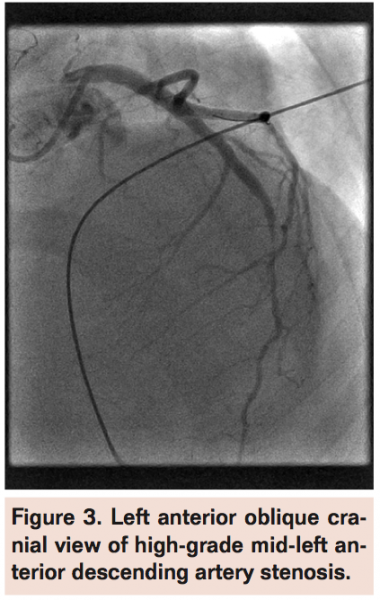

Case Report 2. A 16-year-old female patient with history of orthotopic heart transplantation 10 years prior for ventricular septal defect and secondary dilated cardiomyopathy was referred for PCI from Children’s Hospital Boston. Routine post-transplant angiography revealed rapidly progressive transplant vasculopathy compared to an angiogram performed 6 months prior. She had developed a significant stenosis in the mid left anterior descending artery (LAD) (Figure 3) as well as a significant stenosis in the circumflex artery. She was recently diagnosed with post-transplant lymphoproliferative disorder and therefore was not a candidate for repeat transplantation. She had no specific cardiovascular symptoms but had been experiencing progressive fatigue.